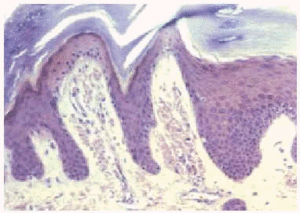

Una biopsia de la lesión cutánea mostró en la tinción con hematoxilina-eosina (fig. 2), un epitelio con una zona de intensa hiperqueratosis, acantosis y papilomatosis con algún cuerpo coloide aislado. En dermis papilar se observaron pequeños depósitos, bien delimitados de una sustancia amorfa, acidófila que daba reacción metacromática con el cristal violeta (fig. 3) y era positiva para rojo Congo (fig. 4). En esa misma zona se observaron incontinencia de pigmento.

Fig. 2.--Epitelio con hiperqueratosis, acantosis y papilomatosis. En dermis papilar, depósitos de sustancia amorfa.